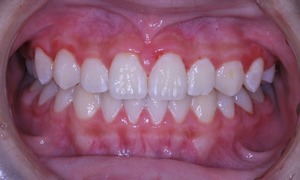

上顎も下顎もそこそこの歯列になっていると思います。

咬み合わせも良好です

なんと、大人の歯は虫歯0本で管理されてます!